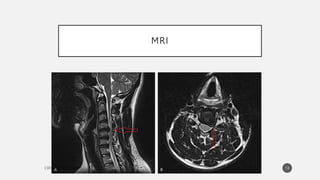

IMAGING

• MRI:

MRI is considered the imaging method of choice for the

evaluation of cervical radiculopathy.

< 40 years : 10% have disc herniations;

>40 years, 20% have evidence of foraminal stenosis and 8%

had disc protrusion or herniation.

MRI